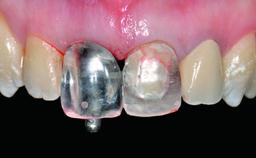

Replacement of an Upper Right Central Incisor with Root Resorption: Ridge Preservation, Delayed Placement of an NC Bone Level Roxolid Implant

A 32-year-old female Caucasian patient with a compromised maxillary right central incisor was referred to us by a general dentist. Her chief complaints were discomfort and mobility of tooth 11 with unsatisfactory esthetics due to discoloration. The patient reported a previous trauma, some years earlier, as the origin of pathology on the afflicted tooth. Anamnesis was negative for any other dental or periodontal pathology in the remaining dentition. The patient did not take any medication and reported to be a light smoker (5–10 cigs/day). She had high esthetic expectations of her treatment. The extraoral examination revealed a high smile line with full exposure of her maxillary teeth and surrounding soft tissue in the area between the second premolars.